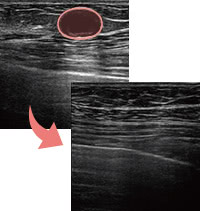

実際のエコー画像

-

施術前

アクアフィリング豊胸のしこりが散在し、一部は塊に -

溶解中

エコー下でしこりにアプローチし、確実に生理食塩水を注入 -

除去したアクアフィリング

完全に溶解しないケースでも、エコー下できれいに吸引除去